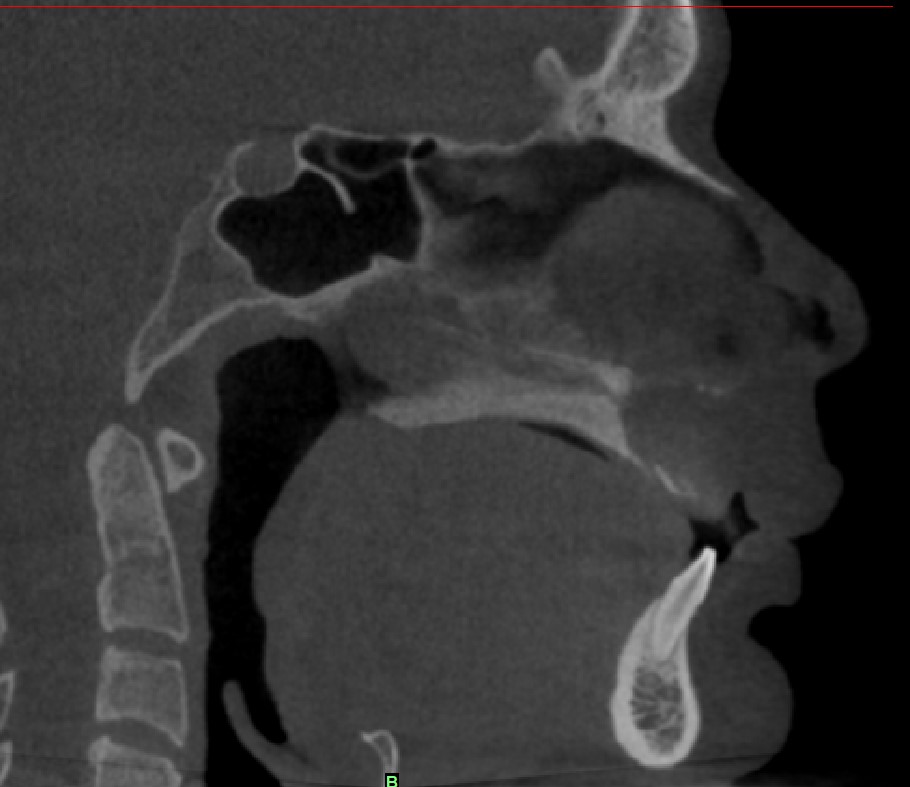

Radiological findings

• CBCT showing well defined unilocular radiolucency with cortical destruction present in anterior maxilla